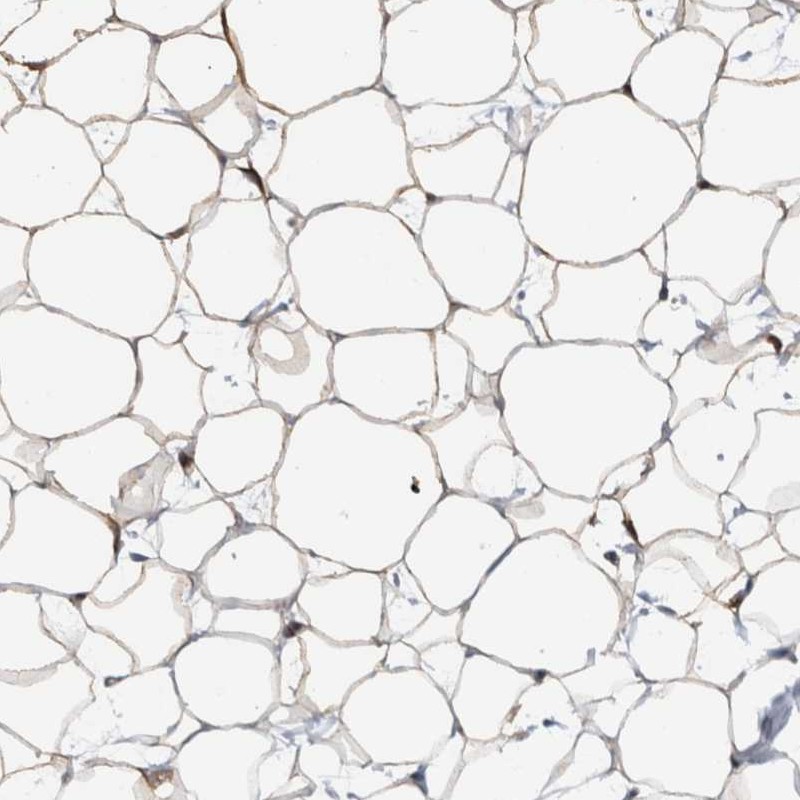

Immunohistochemical staining of human breast shows moderate cytoplasmic positivity in adipocytes.